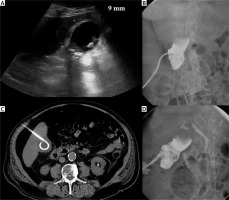

Photo 1

Complication. Acute calculous cholecystitis with infiltration of the gallbladder wall on ultrasound examination (A). Cholecystostomy was indicated due to pneumonia and performed using the transabdominal approach (B). 8 days after the procedure, bleeding into the drain and biliary ducts occurred. The contrast medium enhanced CT in arterial (C) and portal venous phase (D) revealed active hemorrhage (arrows) in the subhepatic space. Angiography was performed with active bleeding verification (E) and therapeutic embolisation with hemorrhage arrest (F)